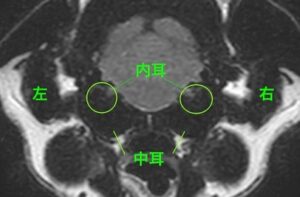

左右の鼓室胞内(内耳)の内腔を占拠する内容物を認める

診断名:両側の重度中耳炎・内耳炎